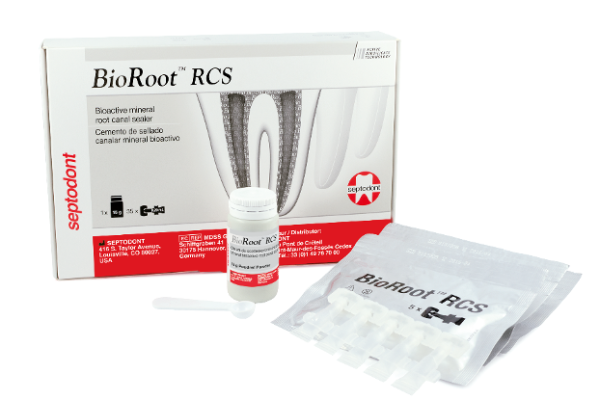

Why is Bioroot RCS changing the way dentists do root canal treatments?

What if you didn’t need to compromise between long term clinical success and an easy, fast technique when it comes…

Bioroot RCS – is a paradigm shift for root canal obturation possible?

Josette Camilleri discusses the composition and properties of the use of Bioroot RCS as a root canal sealer. Introduction The…

Achieve outstanding adhesion to dentine with easy-to-use root canal sealant

Septodont’s, Bioroot RCS is rapidly gaining in popularity. From the same family as its highly regarded synthesised tri-calcium silicate based…